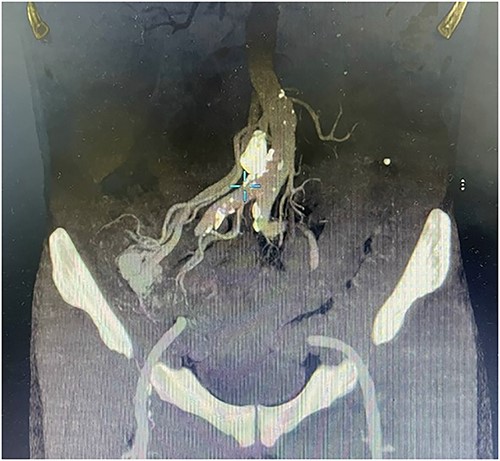

A 57-year-old male patient with a history of hypertension was referred to our hospital for multiple episodes of painless bloody stools for 2 weeks. No gastrointestinal symptoms were observed, such as abdominal pain, nausea or vomiting. A digital rectal examination showed bright red blood. On admission, laboratory evaluation revealed mild anemia with hemoglobin of 103 g/dL. Other than that, there were no other abnormalities. Lower and upper gastrointestinal endoscopy was performed, but the cause of the bleeding could not be identified. Due to the signs and symptoms of ongoing bleeding, we decided to perform imaging tests to make a diagnosis. Abdominal contrast-enhanced computed tomography (CT) revealed a thickened appendix (17 mm in diameter and wall thickening 6.4 mm) without signs of inflammation and images of vascular proliferation and dilated vein around the appendix (Fig. 1). An angiography was performed and demonstrated the AVM of the appendicular artery and vein (Fig. 2).

Contrast-enhanced abdominal CT showed a thickened appendix without signs of inflammation and images of vascular proliferation and dilated veins around the appendix.